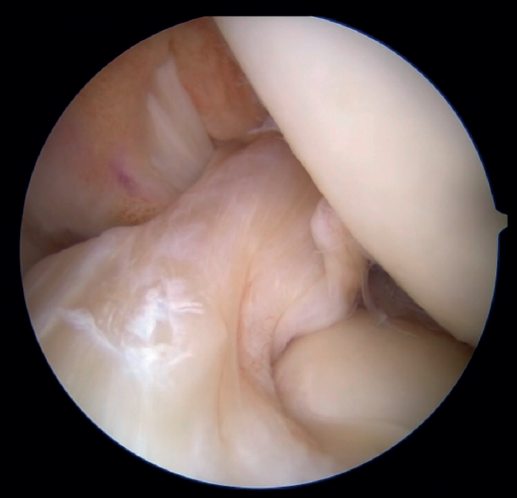

The patient is placed in the supine position and the leg is draped and prepared for knee arthroscopy at the surgeon's discretion, as if an ACL plasty were to be performed. The anterolateral and anteromedial portals are established as usual, and the joint is explored. On exploring the central compartment, it should be confirmed by direct vision and also palpation that the lesion is proximal and that the tissue quality is good; if the tissue is friable and tears easily, repair is not indicated. If the ACL remnant is attached to the PCL, it must be dissected so that the ACL is free and can be manipulated to its insertion site. A blunt shoulder arthroscopy periosteotome is best used for this, although a synoviotome, vaporizer or plasma applicator could also be used, as long as care is taken not to break or burn the tissue and render it non-viable. If there are concomitant meniscal or cartilage lesions, they should be treated earlier in order to avoid forced varus and valgus positions after the repair is completed.

The anteromedial and posterolateral fascicles of the ACL are then identified for suturing separately. Using a suture passer, a closed loop suture is passed through the anteromedial fascicle at its most distal zone, and the loopless extremity is carried alternately (medial to lateral, lateral to medial and so on) to the most proximal zone, usually involving 3 or 4 passes of the suture. The thread may knot on itself during suturing if we are not attentive to it on entry and exit. To solve this problem, we simply undo the knot with retrieval forceps and repeat the step if necessary.

On completion, the thread is retrieved through the accessory anteromedial portal. The process is then repeated, this time with the posterolateral fascicle. To prevent the first thread from breaking with passage of the second thread, it must be ensured that entry and exit in the ligament are very posterior and ideally somewhat proximal to those used for the anteromedial fascicle. Once having reached the most proximal zone after 3 or 4 passes, retrieval is carried out in the same way through the accessory anteromedial portal.